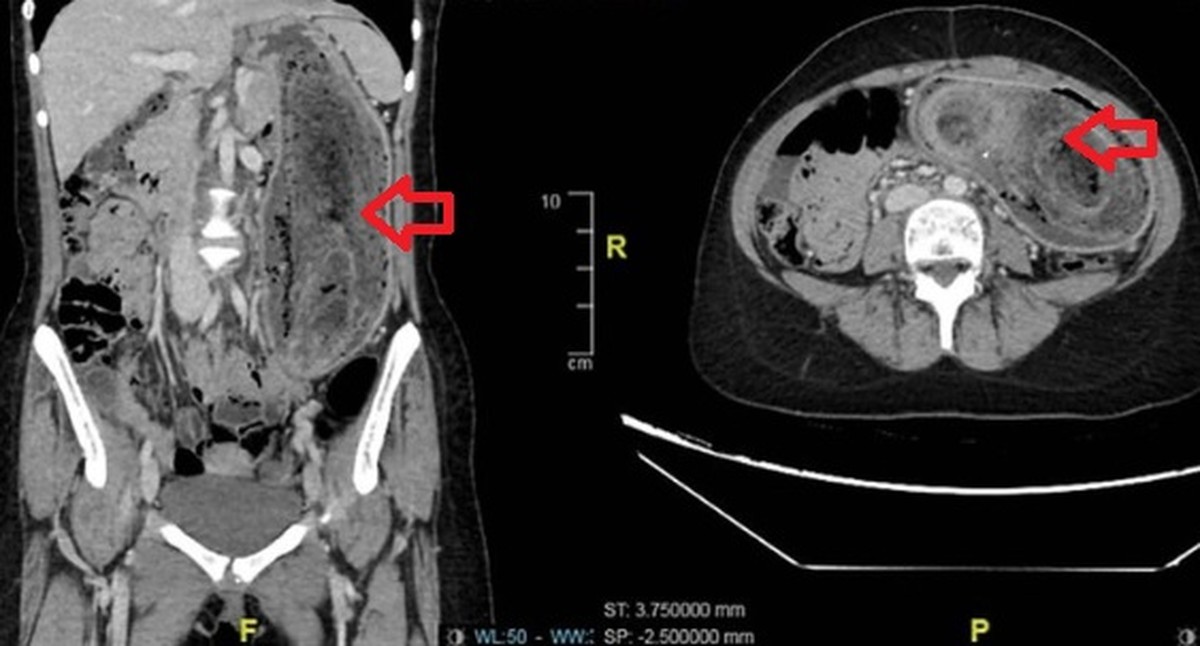

Os médicos notaram que o abdômen estava inchado e dolorido, com uma massa firme palpável. Exames de imagem confirmaram o diagnóstico: um enorme aglomerado de cabelos ocupava todo o estômago e se estendia até o duodeno, o que caracteriza a chamada “síndrome de Rapunzel”.

“Devido ao tamanho, não foi possível remover o material por endoscopia. Foi necessário realizar uma cirurgia aberta sob anestesia geral”, descrevem os autores do estudo. Durante o procedimento, os cirurgiões extraíram cuidadosamente a bola de cabelo intacta, em uma operação que durou cerca de três horas.